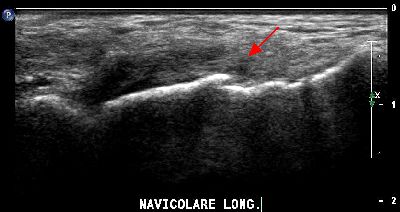

Esostosi scafoidea esostosi scafoidea